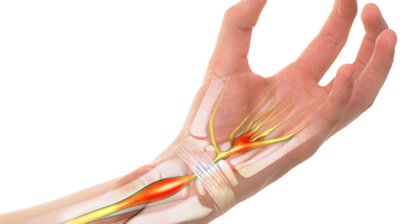

Wenn ein chirurgischer Eingriff notwendig ist, so finden Sie in mir einen Spezialisten für Operationen an Hüfte, Knie und Schulter sowie im Hand- und Fußbereich. Dabei setze ich auf schonende minimal-invasive Methoden.

Handchirurgie